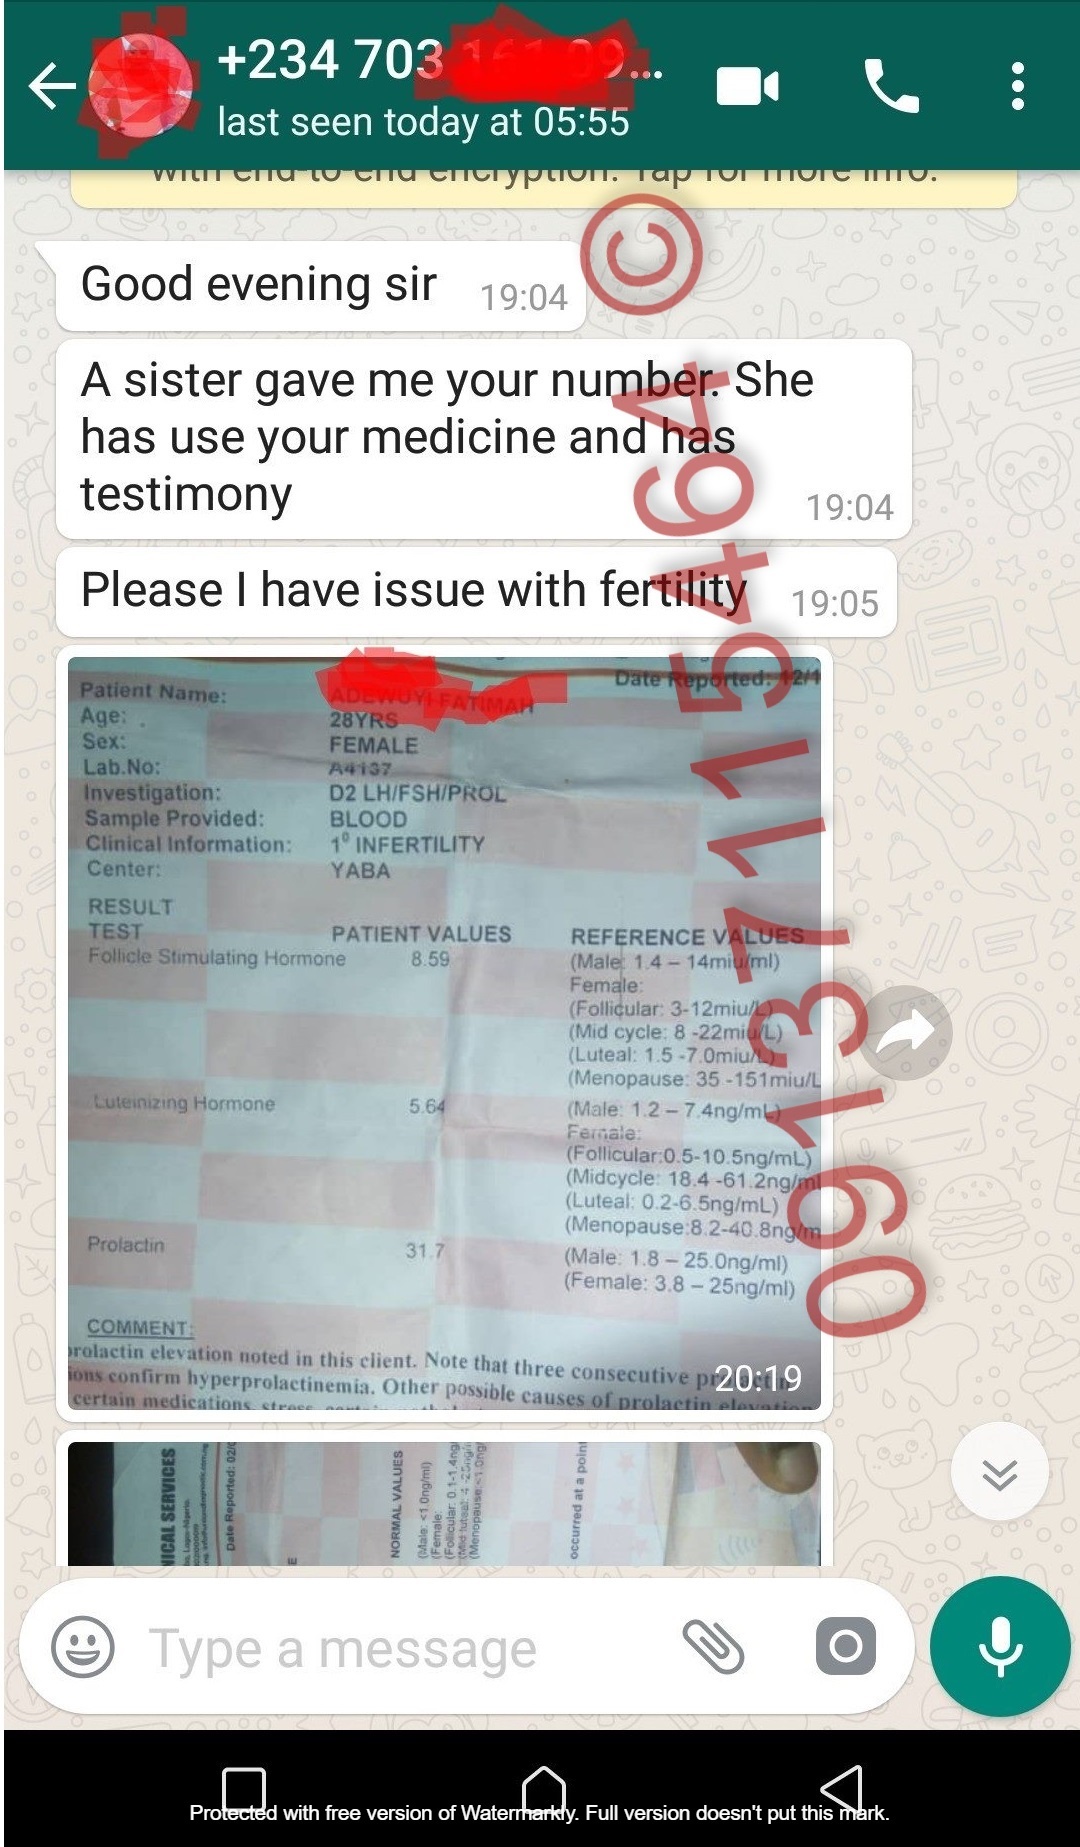

More Testimonials From Those That Used It